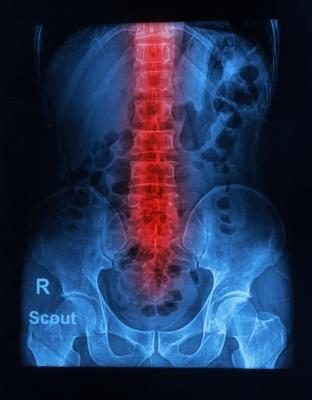

The pain that results from a car accident can affect your extremities such as legs and arms to your torso, neck, and spinal cord. If you feel sharp aches and have trouble moving any of these areas, you should go to the hospital immediately. Should you have cuts, abrasions, and obvious injuries, medical professionals should be called to treat you at the scene of the accident. Bleeding must be stopped and your general medical condition should be under control before you are moved. Immediate injury will also include any chest pains, trouble breathing, or double vision that you may experience after a traumatic accident. If medication is prescribed that does not alleviate your suffering, it’s crucial that you contact the doctor to inform him of this situation. Failure to report any swelling can result in additional injury to your body, or in extreme cases, death. This is not a time to worry about how you will pay for treatment; filing road traffic accident claims can cover any medical costs that you incur as a result of an accident.

A few days after the accident, you may also develop other symptoms that are out of the ordinary for you. If you have trouble swallowing, moving your neck or back, and if you experience continual headaches, you should consult a doctor to ascertain the cause of these abnormalities. The experts advise that you keep all receipts and documentation that pertains to your treatment after the accident. Your team of solicitors will use this information as a basis for the amount of claim that you file for. Make sure that you record exact dates, the other people involved in the accident, and additional details that will make interpreting what happened at the accident easy to unfold.

If you are so sore and stiff that you cannot resume your regular work or household duties, you will need therapy to help restore your range of motion and movement back to its original level. Your doctor will inform you of any therapy that is needed or any special treatment that is recommended to get you back to normal. Be sure to inform your solicitors of any extra treatment or therapy that you will need so that the charge for this can be included in your claim.